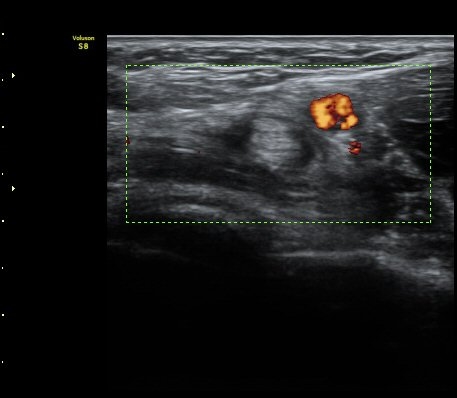

ŽÃËÀÚ¸¦ Á¶±Ý ¸»´ÜÀ¸·Î À̵¿ÇÏ´Ï À̵ιڱ٠ÈûÁÙÀÌ ¶Ñ·ÈÇÏ°Ô °üÂûµÇ°í ÇÔÁÙ ÁÖÀ§¿¡

¼ö¾×Àú·ù°¡  º¸ÀδÙ(±×¸² 3, 4, 5, 6)